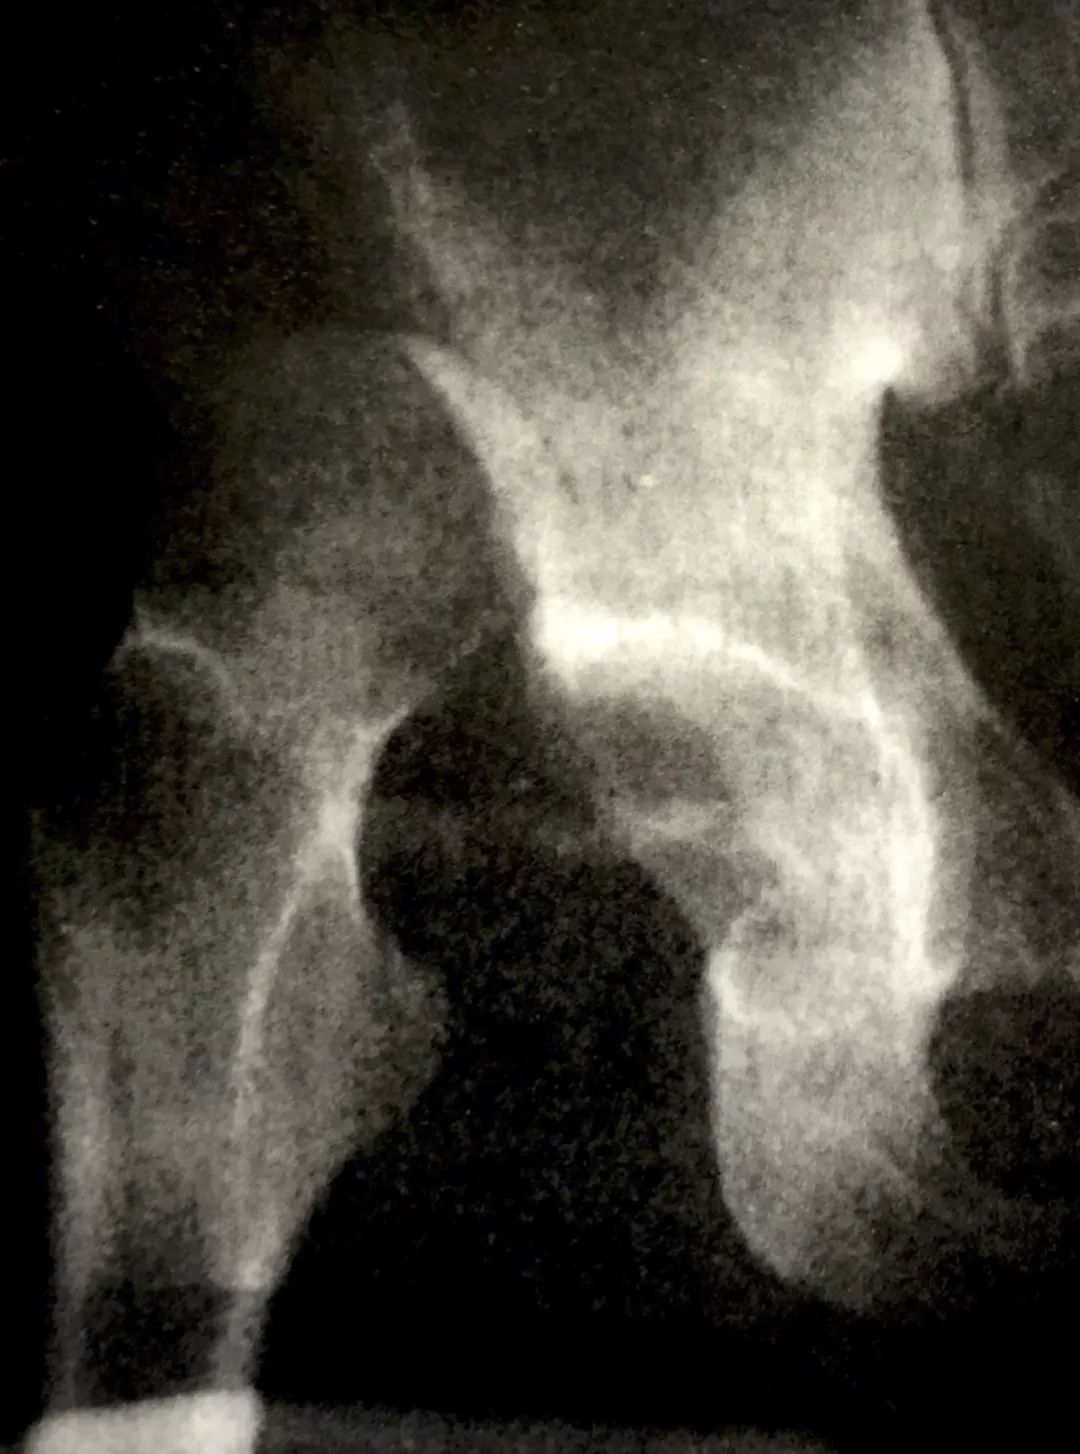

脱位于该线之后者为后脱位。股骨头被挤向中线,冲破髋臼而进入骨盆者为中心脱位。3种类型中以后脱位(图8)最为常见。 这种损伤应按急诊处理,复位越早效果越好。

图8 髋关节后脱位X线片